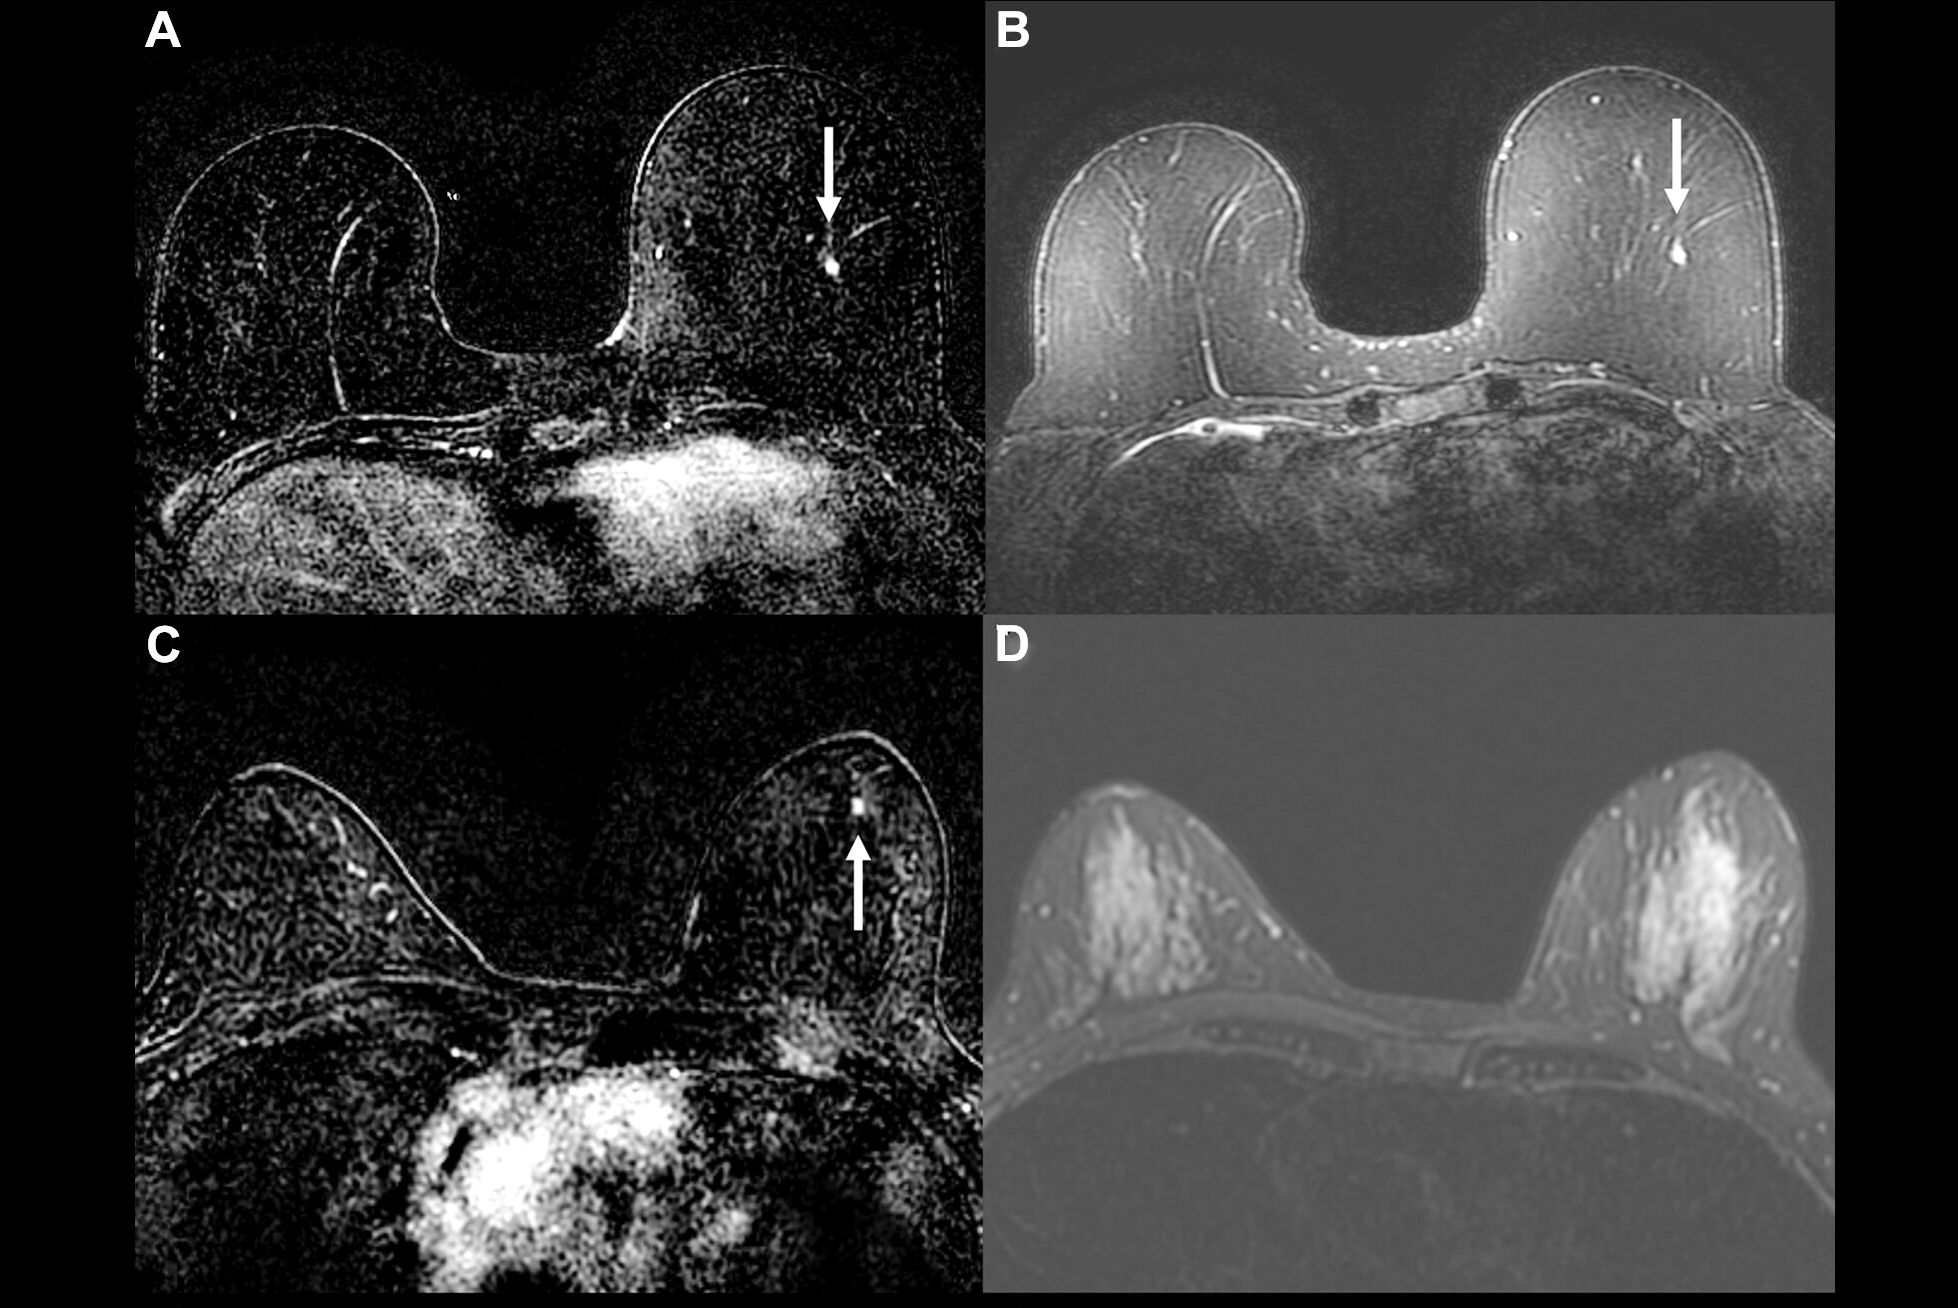

The group sought to create and test a radiomics approach based on DCE-MRI and clinicopathological information to predict pCR and assess different disease-free survival risks after chemotherapy.

The study included 843 breast cancer patients recruited from three medical centers; the total study population was divided into training (n = 385), internal (n = 165), and external (n = 293) validation cohorts. The researchers extracted 944 radiomics features from tumors and 4 mm peritumor regions on dynamic contrast-enhanced (DCE)-MRI images and also took into account clinical-pathological factors such as age, menopausal status, tumor site, estrogen receptor, progesterone receptor, HER2, and histological grading. Finally, Hou and colleagues set the following radiographic characteristics for comparing radiologist performance to the prediction model: tumor edge, tumor morphology, and enhancement mode.